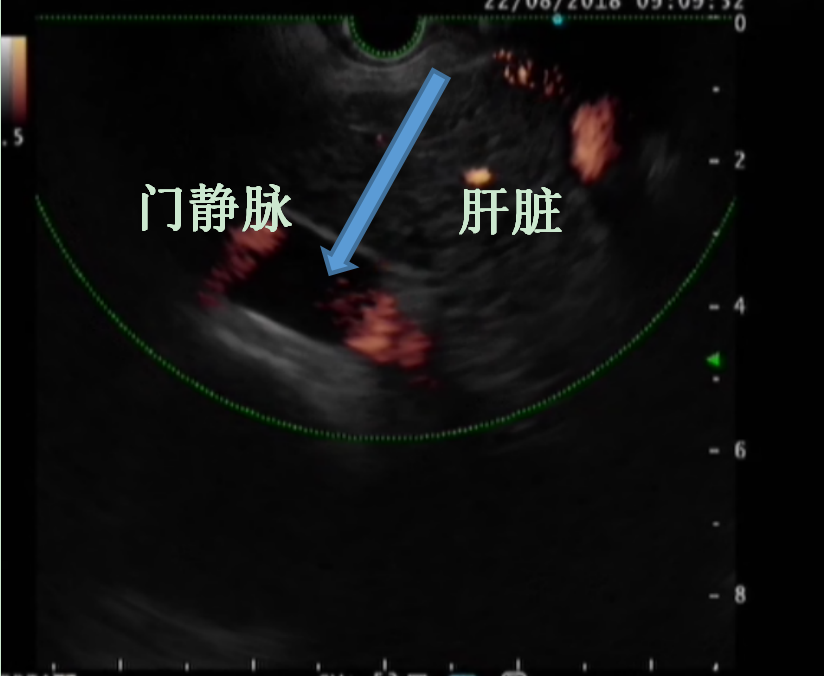

骨髓移植示意图

近期,中南大学湘雅三医院消化内科王芬教授团队采用超声内镜技术将患者自体骨髓经门静脉成功移植到一例乙肝肝硬化失代偿期患者的肝脏内,半月即获得良好疗效,白蛋白水平提升很快,一月后腹水完全消退。

患者是一名50岁中年男性,湖南益阳人,乙肝病史20余年,近年来逐渐出现乙肝肝硬化失代偿期症状:肝功能明显减退、脾功能亢进、大量腹水,多次呕血、黑便,近年来需频繁出入医院。王芬教授在查房时向患者表示可应用“自体骨髓细胞”治疗肝硬化,骨髓中的间充质干细胞可促进促进肝小叶重塑,骨髓造血干细胞在肝脏内可定向分化成新的肝细胞,骨髓自带的细胞因子也可以刺激肝脏原始祖细胞产生新的肝细胞,使产白蛋白的肝细胞数量迅速增加,有望改善患者肝功能、消除腹水、延缓肝硬化进展。在评估患者病情、详细沟通手术相关事项并签署知情同意书后,入院第4天,王芬教授及其团队从患者体内抽出30ml全骨髓,通过超声内镜途径,顺利经门静脉精准定植到肝脏内,术中患者生命体征平稳,未出现明显不适。术后半月随访患者发现,其白蛋白指标由28.9g/L上升到37.8g/L,一月后腹水完全消退。